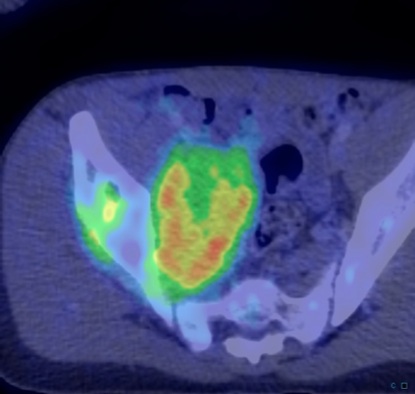

Figure 3 for case Ewing Sarcoma

Figure 3